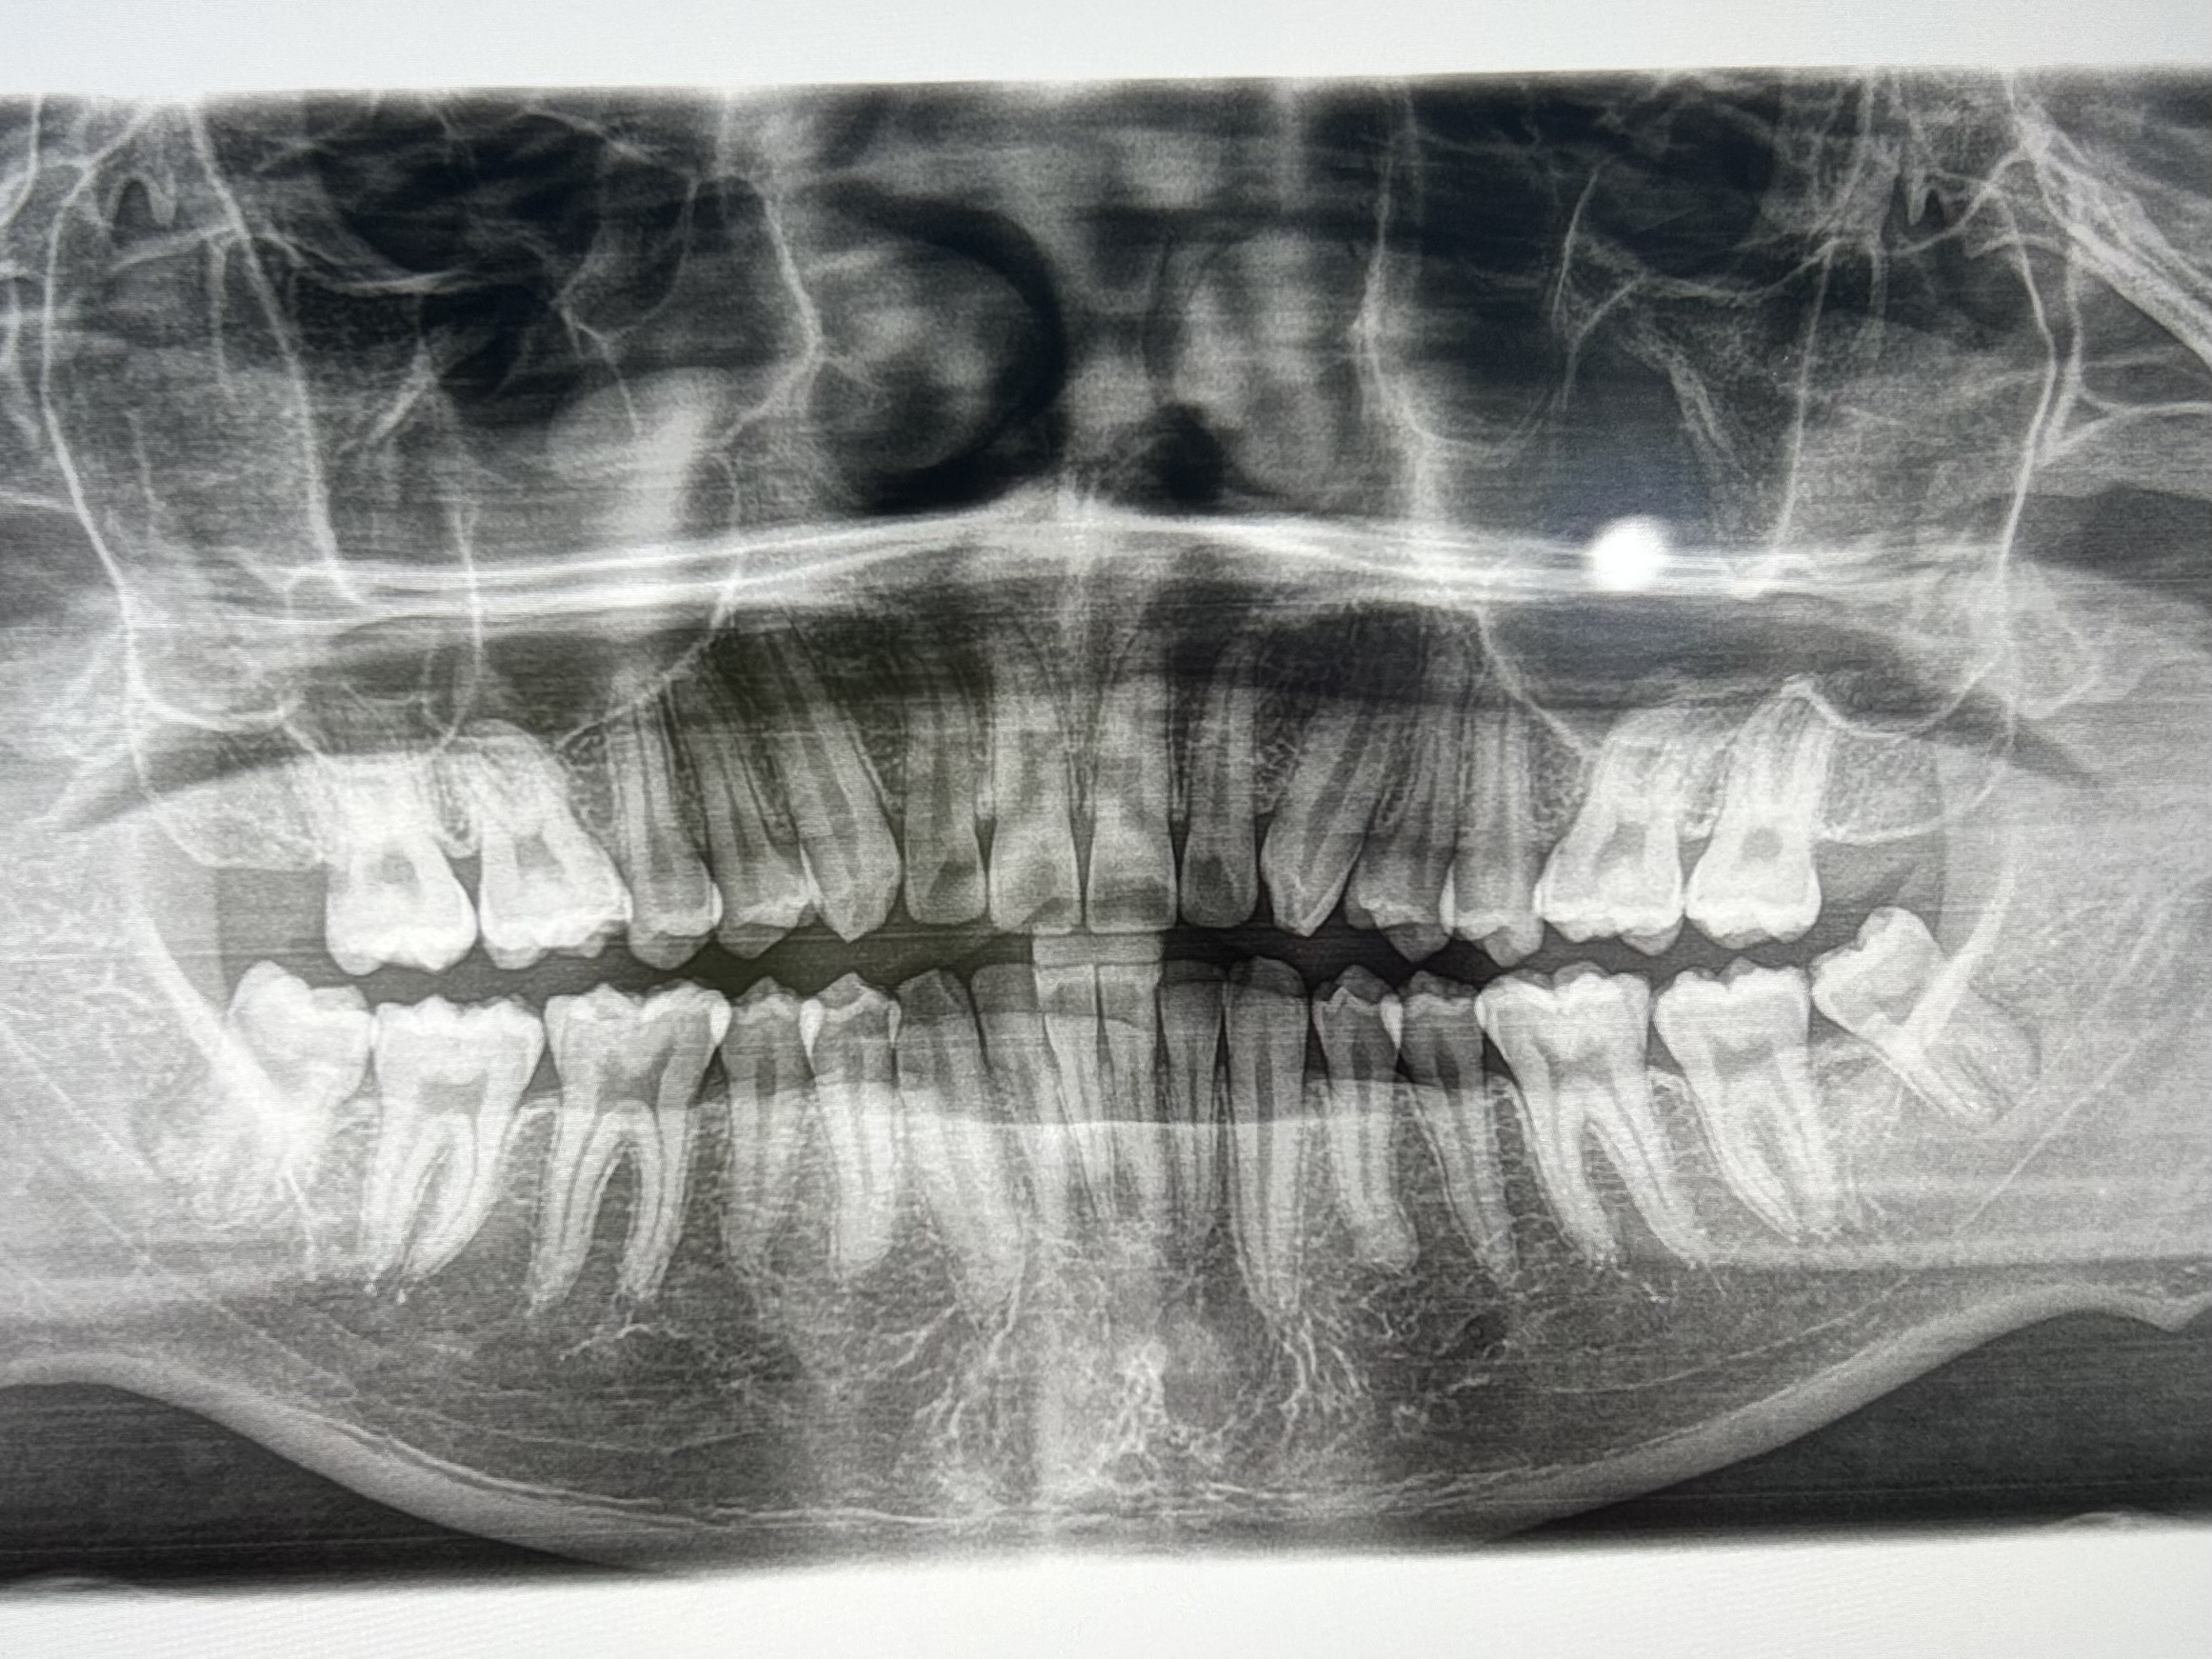

横向きで少しだけ生えている親知らずが痛みます。早めに抜くべきですか?

斜めに生えている親知らずの抜歯を勧められています。